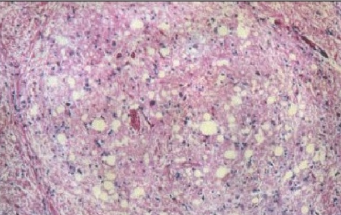

При болезни куру патологические изменения можно наблюдать только в центральной нервной системе. Обычно они выражаются в формировании типичной губчатой энцефалопатии. В коре, подкорковых ядрах, подбугорной области и в мозжечке наблюдается вакуолизация дендритов, аксонов и тел нейронов. Вакуолизация становится настолько выраженной, что серое вещество коры большого мозга приобретает вид губки, в результате чего такое состояние обозначают как status spongiosus. Методом электронной микроскопии было выяснено, что вакуоли окружены фрагментами таких же пролиферирующих мембран. Характерный патогистологический признак при куру – выпадение нейронов.

Изменения нейронов сочетаются с гипертрофией и размножением астроцитов. При куру у человека патогистологические изменения наиболее выражены в мозжечке: появляются аморфные ШИК-положительные бляшки, содержащие амилоид, уменьшается количество грушевидных нейронов (клеток Пуркинье). Вместе с тем, при куру не удаётся обнаружить воспалительной реакции, столь характерной для многих заболеваний ЦНС, или таких характерных признаков вирусной инфекции, как образование телец включений или глиальных узлов.

Таким образом, морфологически прионные болезни можно отнести к группе амилоидозов. Амилоидоз при прионных болезнях характеризуется отложением волокнистого амилоидного белка в головном мозгу. Образование прионных амилоидных бляшек сближает прионнные болезни с амилоидозами из группы нейродегенеративных заболеваний, таких, как, например, хорея Гентингтона. Получены убедительные доказательства того, что свойства прионных белков и амилоидов идентичны.

Тем не менее, при большом сходстве патогистологических изменений между болезнями Крейтцфельдта-Якоба, куру и скрепи имеются отличия. Так, амилоидные бляшки при болезни Кройцфельдта-Якоба наблюдаются в 9%, а при куру они встречаются в 70% случаев.

Уже давно было подмечено, что все симптомы при болезни Кройтцфельдта-Якоба подкрепляются патогистологическими изменениями. Так, при изменении моторных нейронов отмечено выпадение многих нервных клеток в двигательной области коры, включая гигантские пирамидные нейроны (клетки Беца), а также демиелинизацию пирамидных путей и утрату клеток передних рогов спинного мозга.

болезни Кройтцфельда-Якоба